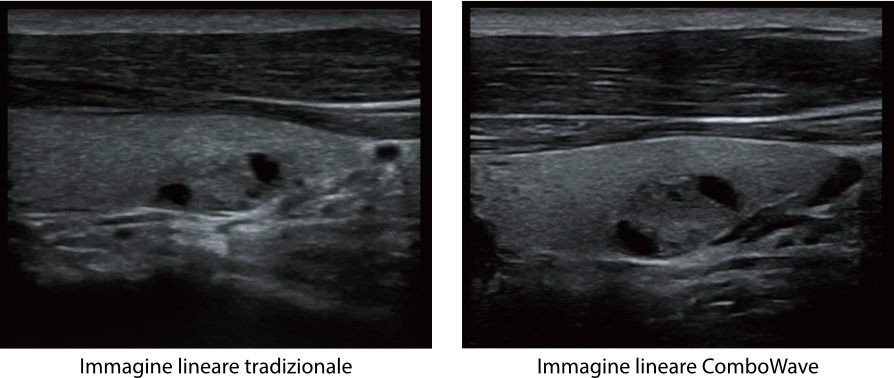

Trasduttori ComboWave

ComboWave utilizzano un nuovo tipo di materiale piezoelettrico composito per ottimizzare efficacemente lo spettro acustico e ridurre l'impedenza acustica. Se integrati con la tecnologia 3T, distintiva di Mindray, i trasduttori lineari ComboWave garantiscono prestazioni eccezionali con risoluzione dâimmagine e uniformitĂ eccezionali nelle applicazioni relative a tiroide, seno, vascolari e altro ancora.